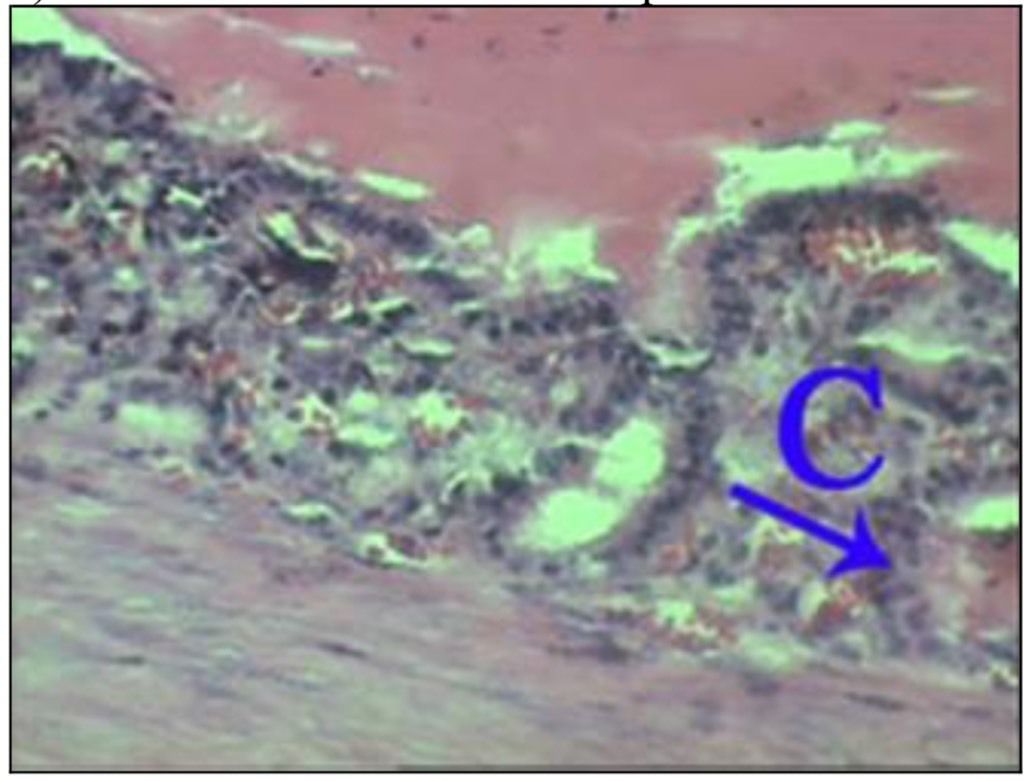

Question 67

Question

What is the correct answer at point A?

Answer

• - cristaux d’urate de sodium

• - dépôt d’urate de sodium

• - granulome à corps étranger

• - cellules inflammatoires

• - cellules géantes à corps étranger

Question 68

What is the correct answer at point B?

Question 69

What is the correct answer at point C?

Question 70

What is the correct answer at point D?

Question 71

What is the correct answer at point E?